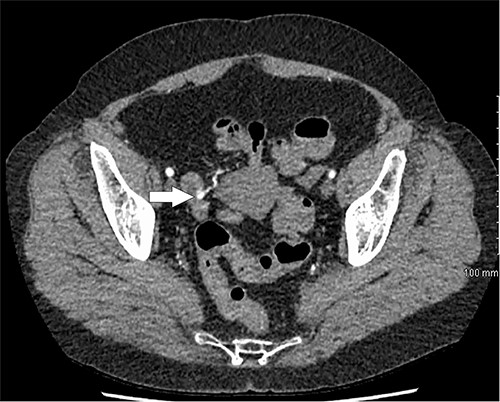

Further episodes of rectal bleeding were noticed the following day, and the hemoglobin level dropped significantly, requiring blood transfusions. An urgent computed tomography (CT) mesenteric angiography was performed, which demonstrated the extravasation of contrast in a segment of distal ileum (Fig. 1), ~30 cm from the ileocecal valve, suspicious for angiodysplasia. She subsequently underwent a laparoscopy, which was converted into a lower-midline laparotomy due to dense omental adhesions secondary to prior appendectomy and cesarean sections. After adhesiolysis, small bowel was thoroughly examined. The terminal ileum contained blood, while proximal small bowel appeared unremarkable. About 30 cm from the ileocecal valve, a small transmural lesion was noticed, which was red and blanching in appearance (Fig. 2). A segmental resection of ileum was performed, and the specimen was cut open to demonstrate the luminal aspect of AVM (Fig. 3). A primary anastomosis was performed. Histology showed a small, non- encapsulated nodule, composed of complex clusters of thin and thick-walled blood vessels, abnormally located in the submucosa (Fig. 4). Post-operatively, the patient had an uneventful recovery and was discharged home well after 4 days.

CT mesenteric angiogram showing contrast extravasation in distal ileum.